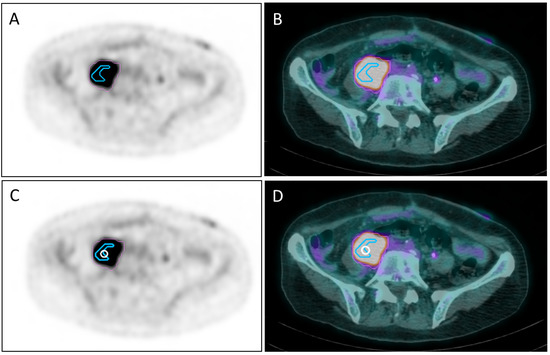

2.2.1. Vertex Positioning and Treatment Planning for Bulky Disease